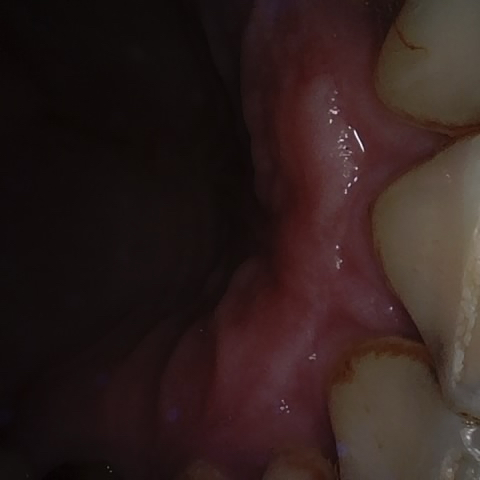

Image 357 / 1743

NHD36692

Annotated as "Good"